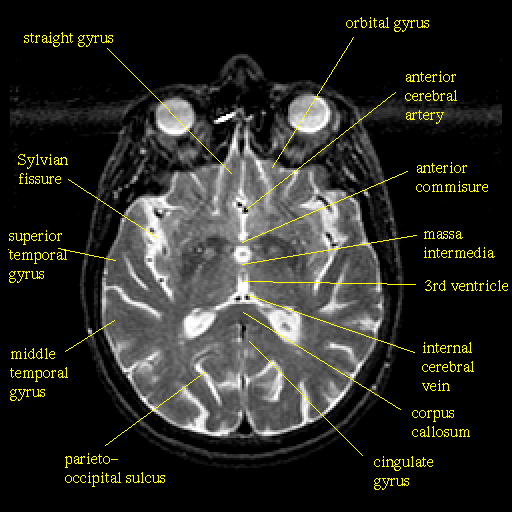

Study Page for First Quiz Below is a labelled study image for the first brain quiz. Notice that more structures are labelled in this figure than you are asked to identify in the quiz.

Return to the first brain quiz.

Images are from the The Whole Brain Atlas.